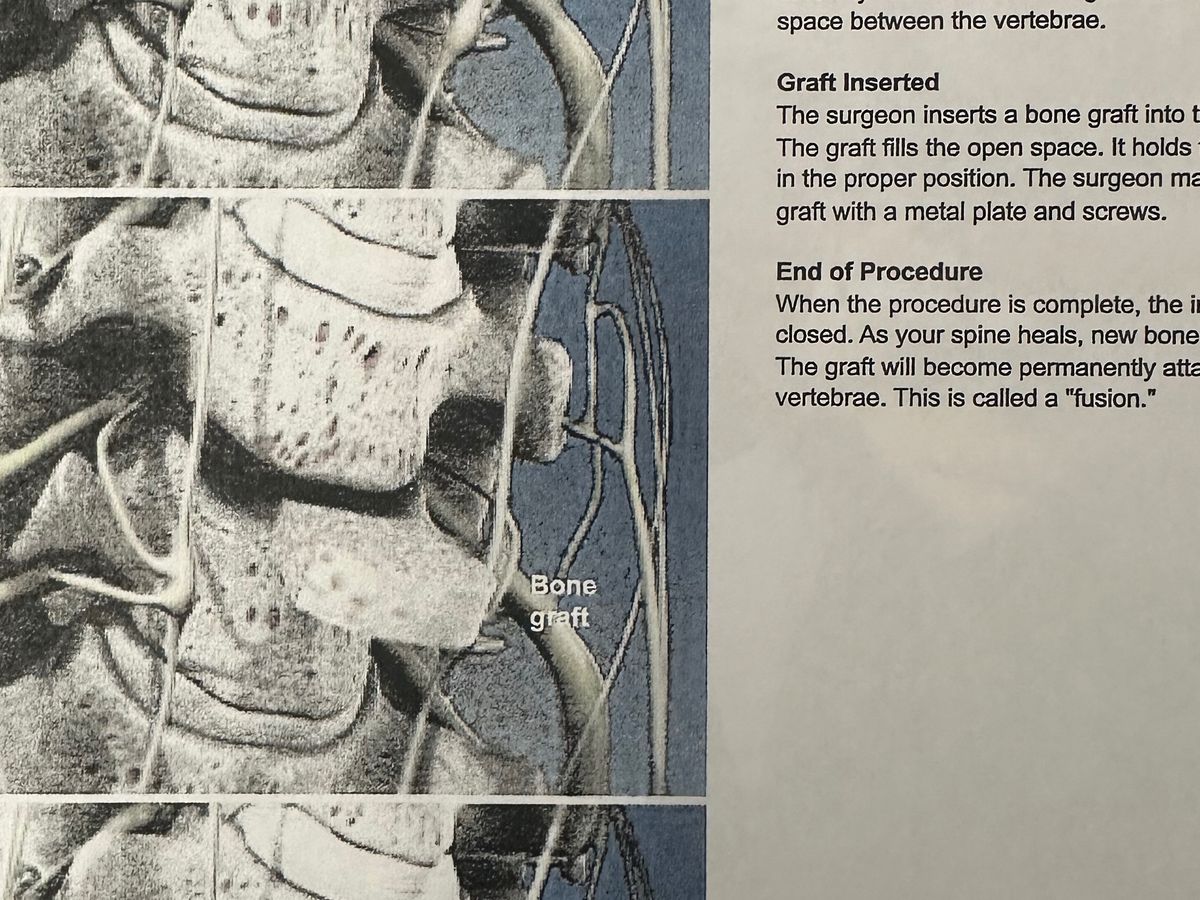

For over a year, I've had a pain in my neck and right shoulder blade. I thought I pulled something. Fast forward to May of this year. X-rays showed a narrowing of my cervical spine. I was sent to physical therapy. After 8 weeks of no relief, the PT recommended I have a follow-up appointment with my primary provider. Then they ordered an MRI. The results showed nerve damage caused by the degeneration of my C6-C7. I was then referred to a neurosurgeon at Bronson Methodist. The neurosurgeon recommended a fusion surgery that will most definitely help me. My surgery is scheduled for October 7.